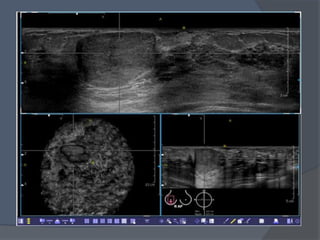

 La elastosonografía es una técnica que

 Esta modalidad añade información

que nos muestra la ecografía.

 Correlación de los mapas anatómicos de

 Muestra el resultado en escala de color

ASPECTOS TECNICOS

 El ecógrafo mediante el cual se realizan

 Utiliza el mismo transductor para los

 Habitualmente se evalúa la lesión en modo

 Los datos se traducen a una escala de colores

 Los colores oscilan entre:

Una puntuación de 1 o Score 1 (E1) indica una tensión o elasticidad

Una puntuación de 2 (E2) indica una lesión

Una puntuación de 3 (E3) indica elasticidad en la periferia

Una puntuación de 4 (E4) indica ausencia de

Una puntuación de 5 (E5) indica ausencia de elasticidad en

 La elastografía, al complementar la ecografía de

 Evitar falsos positivos en lesiones con scores

 Ayuda a detectar aquellas lesiones incluidas en

 Tras la elastografía pueden beneficiarse de un